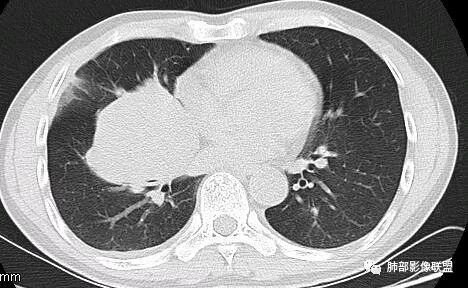

这一个类圆形,边界光滑,明显膨胀生长为主,如果起源中叶支气管,按理中叶支气管不动,固定在中叶支气管上,推移其他结构

但是现在的片显示,其主体在下叶,中叶支气管壁由下朝上有推移

南边:就不符合这个原理

初学者:如果中叶病灶,叶间裂应该下推,也不会上推

而且支气管內密度较高是粘液栓,远端支气管也是通畅,所以支气管内是因为受压所以痰液引流不畅。

南边:病灶边界清,提示侵袭性弱,膨胀生长为主;这时候我们提示病灶不应该是支气管关系密切,提示间叶来源或胸膜来源